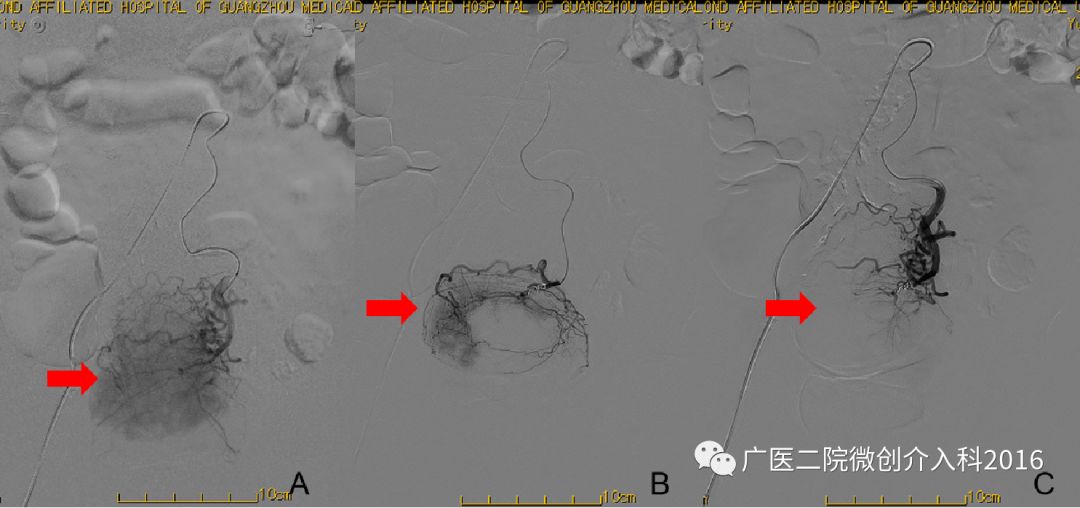

病例3:胆道出血

患者为经皮胆道取石术后胆道出血,经内科药物治疗无效,仍有大量出血。图A行肝动脉造影,右肝可见造影剂外溢并呈囊状扩张,表示正在出血。图B行介入栓塞治疗,注入不同规格的弹簧圈行出血动脉栓塞术。图C再次造影可见原出血征象消失,患者胆道出血停止。